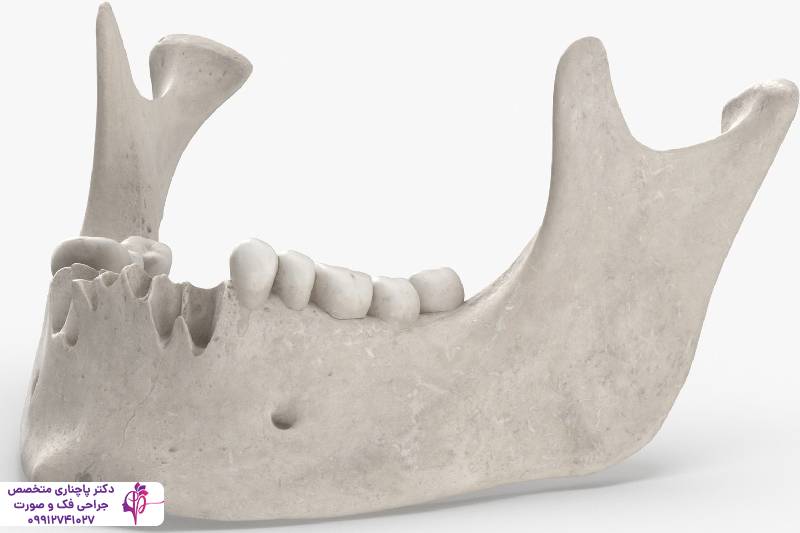

قبل از اینکه با علائم و روش درمان تحلیل استخوان فک آشنا شویم بیایید ببینیم دقیقا منظور از تحلیل استخوان فک چیست. وقتی بافت استخوانی کاهش پیدا میکند و حجم و تراکم خود را از دست میدهد و ضعیف میشود در واقع تحلیل استخوام فک اتفاق افتاده است. استخوان فک که دندانها را در جای خود نگه میدارد مثل یک ستون برای ساختار صورت عمل میکند. در حالت عادی استخوان فک در یک چرخه طبیعی مدام بازسازی میشود. در این چرخه سلولهای استئوکلاست استخوان قتدیمی را تجزیه میکنند و سلولهای استئوبلاست استخوان جدید میسازند. وقتی این تعادل به هم میخورد استخوان تراکم خود را به تدریج از دست میدهد. یکی از مهمترین دلایل به هم خوردن این تعادل افتادن دندانهاست، وقتی دندانی در استخوان فک وجود ندارد عملا نیرویی برای جویدن اعمال نمیشود و بدن استخوان فک را یک ناحیه غیرضروری تلقی میکند و کاری هم برای تقویت آن انجام نمیدهد.

این اتفاق به تدریج جلو میرود و گاهی علائم تحلیل استخوان فک با گذر زمان و پیش آمدن مشکلات جدیتر خودش را نشان میدهد. مشکلاتی مثل ناتوانی در استفاده از پروتزهای دندانی یا تغییر شکل صورت از این قبیل مشکلات هستند. تحلیل استخوان فک در افراد مسن بیشتر اتفاق میافتد چون در این افراد سرعت بازسازی استخوان کم میشود. گرچه عوامل محیطی و سبک زندگی هم نقش مهمی در این مورد دارد.